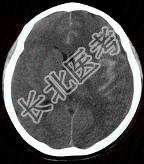

- 单项选择题成年男性,外伤后一小时出现头痛, 呕吐,查体: 颈项强直。CT检查如图,最可能的诊断是 ( )

A、硬膜外血肿

B、脑出血

C、正常脑CT

D、硬膜下血肿

E、蛛网膜下隙出血